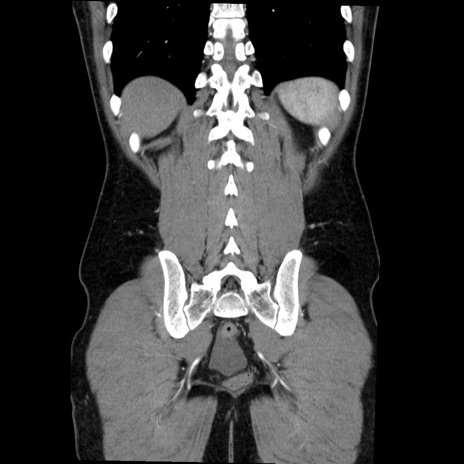

症例36(冠状断像)

【症例】20歳代 男性

【主訴】心窩部痛

【現病歴】今朝より上腹部痛あり。一旦軽快していたが再度出現したため救急要請。昨日夕に白身の魚を含む刺身を食べた。

【身体所見】BP 136/89mmHg、HR 74/min、BT 37.0℃、腹部:膨満、軟、心窩部に圧痛あり。反跳痛なし、筋性防御なし、腸雑音やや亢進あり。

【データ】WBC 17700、CRP 0.48